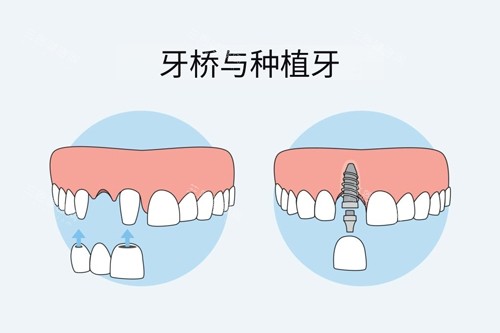

本文将解析乐山英美口腔在种植牙领域的优势,包括医生团队的背景、设备配置的丰富性、2025年价格体系、特色服务项目以及真实患者评价,为有种植牙需求的朋友提供详实的参考信息。

值得一提的是,乐山英美口腔在本地服务已有多年的历史积淀,通过不断引进新技术、新设备,逐步发展成为集种植牙、正畸、美学修复、儿童齿科等为一体的综合性口腔医疗机构。特别是在种植牙领域,医院投入了大量资源,建立了专门的种植中心,为不同需求的患者提供多样化的解决方案。